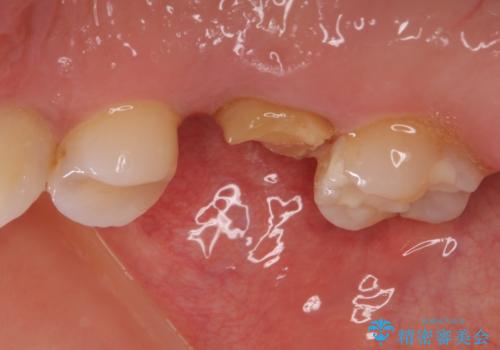

- 近医で奥歯の抜歯が必要であると指摘され、インプラント治療を希望して来院された患者様です。

診察の結果、大きな虫歯となっている歯は抜歯が望ましく、抜歯後にストローマンSLActiveを埋入することとしました。

さらに後方の歯は虫歯治療が途中であったため、ゴールドインレーにて修復治療行うこととしました。